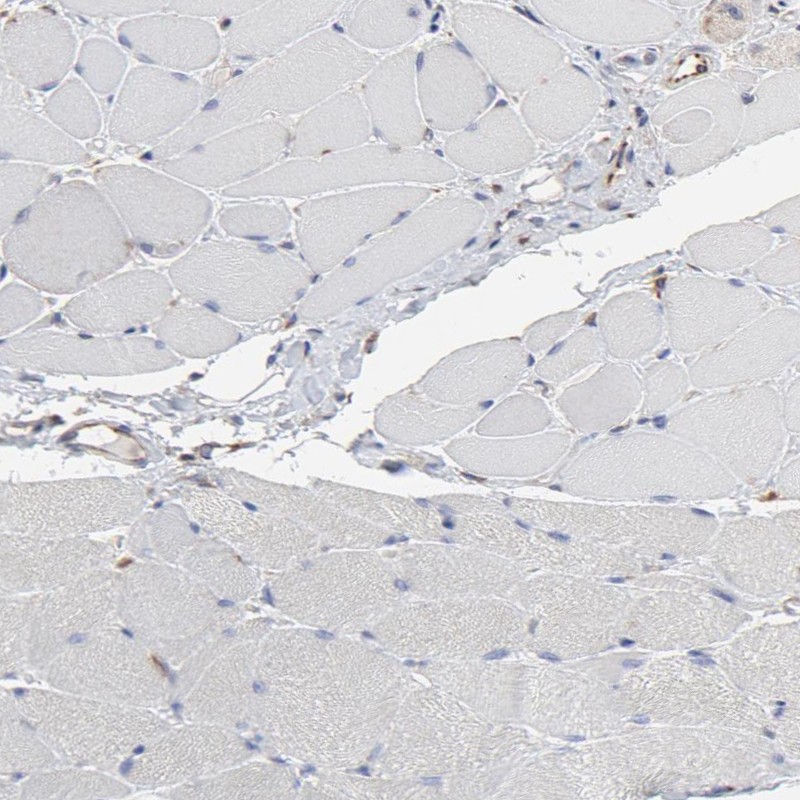

Immunohistochemistry analysis in human adrenal gland and skeletal muscle tissues using Anti-RAB9A antibody. Corresponding RAB9A RNA-seq data are presented for the same tissues.